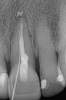

(1.) Peri-implantitis bone loss.

Figure 1

(2.) Peri-implantitis bone loss.

Figure 2

Peri-implantitis is defined as a bacterial plaque-associated pathological condition related to oral biofilm occurring in tissues around dental implants, characterized by inflammation in the peri-implant mucosa and subsequent progressive loss of surrounding bone1-8(Figure 1 and Figure 2). Food impaction is a contributing but not a primary factor in the disease process.